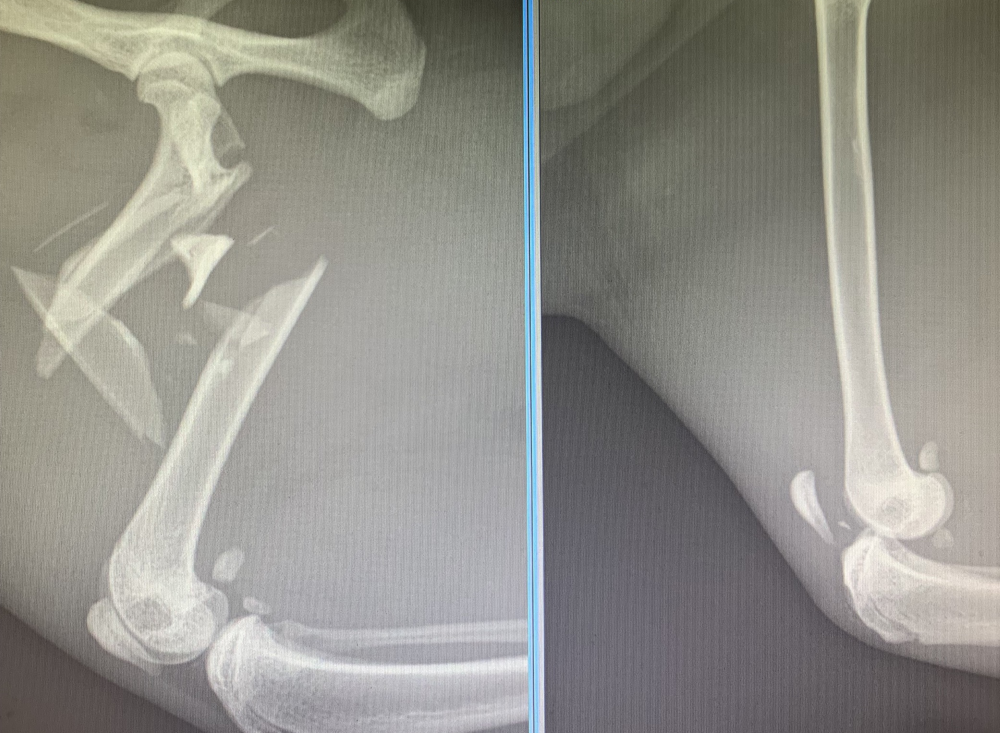

When Tygg first arrived at Davies, X-rays confirmed the gravity of the situation and it was clear the intricate surgeries would require great skill and greater teamwork.

“Tygg’s injuries were extensive and affected both sides. The femur (thighbone) was shattered into many pieces and very close to his hip. His left leg was no better; all the ligaments of his left knee had to be reconstructed.

Alberto added: “The operations were very challenging due to the number, severity and location of the injuries. There was not much bone available to fix his femur. An external fixator (external frame) was placed to hold the small main fragments stable while his body was healing.